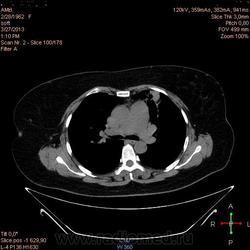

Здравствуйте, коллеги .Нужна помощь.Больная страдает Бронх.астмой.Беспокоять кашель,одышка , слабость, боль левой грудной клетке.Была температура 37,5- 38,0.Данный момент получает цефомизин темпер нормализовалось.Хочеть стационарное леч.Обратите пожалуиста на молочные железы, справа была операция год назад .Беспокоять боль правой мол.железе.

Во-первых, нет дайкомов. По представленным изображениям, изменения в левом легком дифференцировал бы между ТЭЛА мелких ветвей и организующей пневмонией, справа - пока вариантов нет (нужны дайкомы).

+1. Диф. диагностика между ОП и ТЭЛА обоих легких. Исключить ТЭЛА методом КТ с в/в боюсным контрастированием.